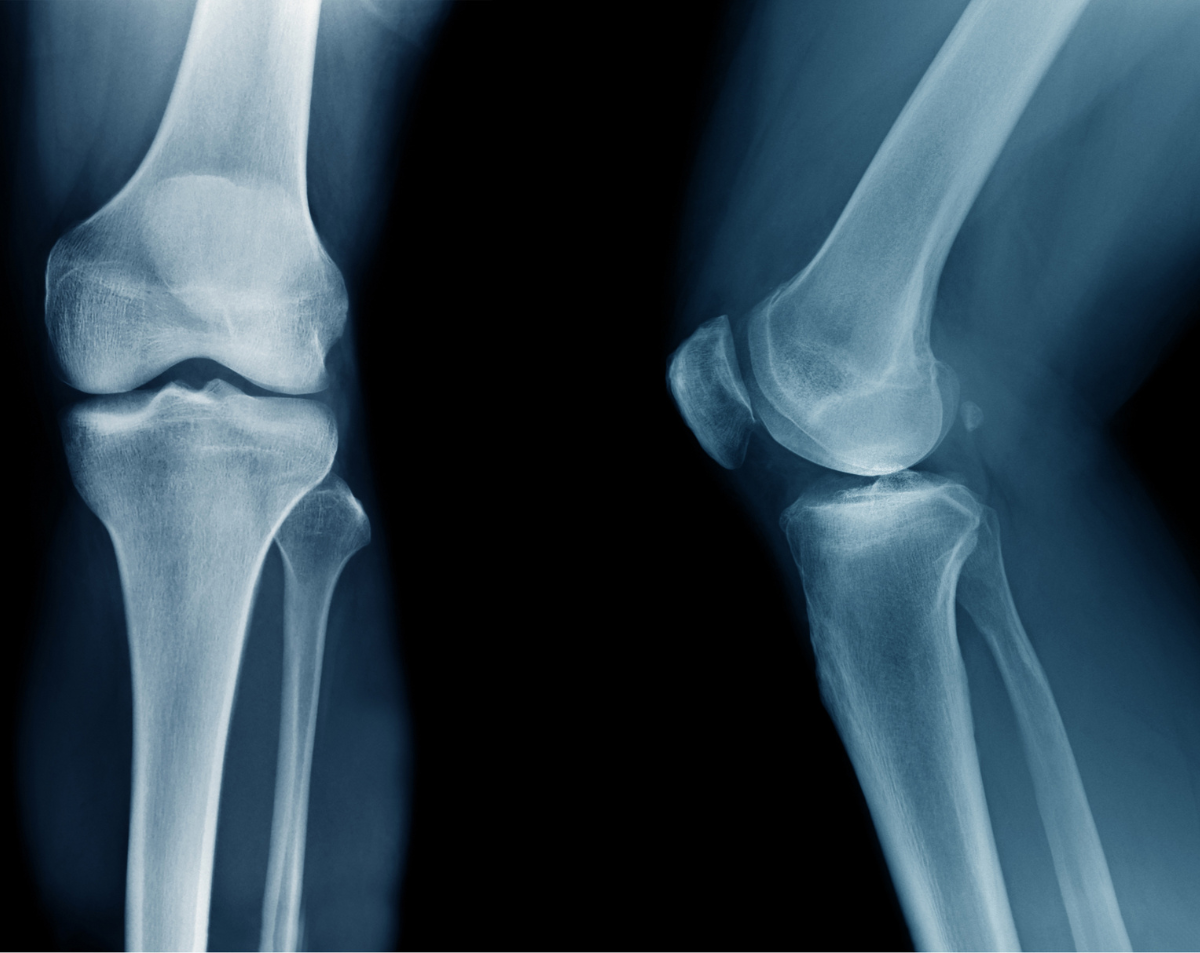

A left knee X-ray produces detailed images of the knee joint, including the femur, tibia, fibula, and patella. Physicians often order this test to evaluate injuries, detect arthritis, monitor post-surgical healing, or investigate persistent joint pain. At Desert Mobile Medical, we bring hospital-grade mobile X-ray technology directly to you—so you get accurate results quickly, privately, and without the hassle of urgent care or hospital visits.